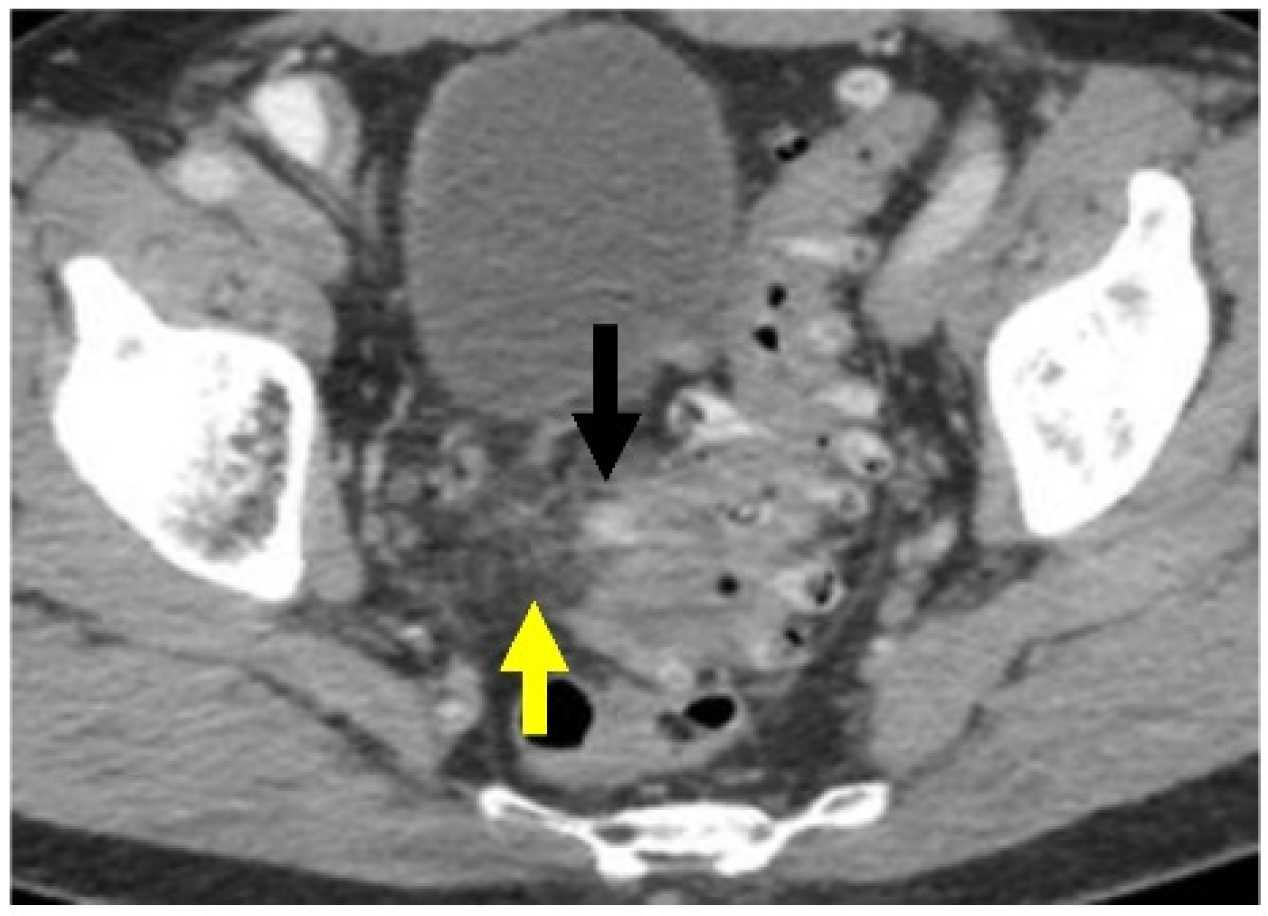

Histologically, diverticulitis shows inflammation of the diverticular pouch with or without mucosal ulceration. When the diverticular pouch is ruptured, subserosal abscess can form (Figure 3). Computed Tomography (CT) with intravenous (IV) contrast is the imaging modality of choice to evaluate for acute diverticulitis and its complications [27].

Figure 3.

Diverticulitis: H&E stain shows a diverticulum (circle) with acute inflammation and abscess formation in the peri colonic adipose tissue in the sigmoid colon (H&E, ×25).

Most patients (~90%) will have uncomplicated diverticulitis, characterized by localized inflammation limited to the colonic wall and surrounding tissue. Patients present with fever, abdominal pain, and/or leukocytosis [4,26]. On CT imaging, there is evidence of inflammatory stranding within the peridiverticular fat without evidence of free air or an adjacent fluid collection (Figure 4).

Figure 4.

Acute uncomplicated sigmoid diverticulitis. Axial CT image through the pelvis with oral and IV contrast. There is extensive sigmoid diverticulosis. There is inflammatory stranding within the fat (yellow arrow), which is centered on a sigmoid diverticulum (black arrow). There is no evidence for free air or adjacent fluid collection.